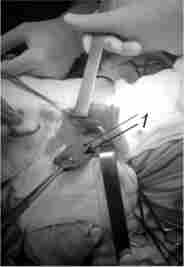

Мал. 9.15. Операція видалення дивертикула Ценкера:

1 - виділений до шийки дивертикул Ценкера

Основна операція - видалення ДП. Для видалення дивертикулу Ценкера застосовують лівобічний доступ по передньому краю грудинно-ключично-соскоподібного м'яза. Цю м'яз і судинний пучок шиї відводять латерально, а щитовидну залозу з трахеєю - медіально. Знаходять і виділяють дивертикул до шийки (рис. 9.15).

Для кращої візуалізації використовують спосіб ендоскопічної «підсвічування» дивертикула. Його відсікають після накладення на шийку зшиває апарату. Потім роблять розсічення крікофарінгеальной м'язи - з урахуванням її ролі в патогенезі захворювання - протягом 1,5-2 см без пошкодження слизової стравоходу.